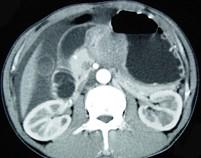

问题 男,65岁,中上腹痛腹胀、消瘦、乏力、纳差,影像检查如图,最可能的诊断是 ( )

选项 A.胃间质瘤 B.萎缩性胃炎 C.肥厚性胃炎 D.胃窦癌 E.胃淋巴瘤

答案 D